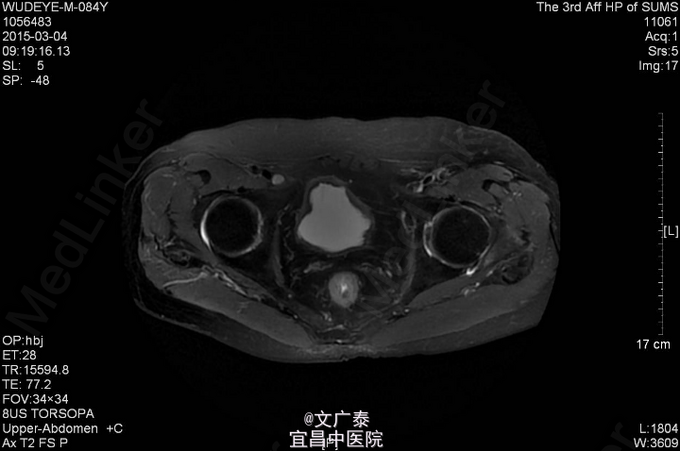

1、TURP加双侧睾丸切除术后11年 2、患者于11年前在本院行前列腺电切术加双侧睾丸切除术后,术后病理回报:前列腺腺癌,(Gleason评分:4+5=9分)。术后予以康士得(50mg qd )内分泌治疗2年后改用福至尔(250mg tid)治疗至今。复查tPSA: 2011.02 tPSA:1.00 ng/L,2012.02 tPSA:0.804 ng/L,2013.02 tPSA:1.23 ng/L,2014.11 tPSA:2.57 ng/L。

3、直肠指检:肛门括约肌正常,前列腺不大,无触痛,表面光滑,质韧,边缘清楚,中央沟存在,未触及明显结节,指套未见染血。余无异常 4、盆腔MR:前列腺癌术后。核素PET/CT全身:1.前列腺癌术后,局部软组织灶,未见明显异常代谢,考虑疤痕形成可能性大;